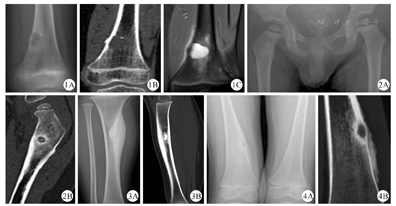

影像学检查结果:3例骨质破坏周围无硬化骨(典型病例见图1),17例骨质破坏周围有硬化骨(典型病例见图2),4例骨皮质增生肥厚(典型病例见图3),5例股骨远端外翻畸形(典型病例见图4)。

本研究中,17例干骺端局部骨质破坏,大小不一,诊断为Brodie脓肿,其中7例表现为干骺端较大的类圆形或者椭圆形破坏灶,首诊通过X线检查就能发现,不易漏诊;10例表现为紧贴干骺端骨皮质微小破坏灶,局部伴或不伴骨膜反应,可伴有骨质硬化,X线检查表现不明显,需借助CT扫描重建识别,同时需与骨样骨瘤相鉴别。3例患儿胫骨干局部骨皮质成梭形增生肥厚,首发症状以触及小腿肿物就诊,无明显疼痛,诊断为Garré骨髓炎。余2例股骨颈局部骨皮质破坏表现为"虫蚀样"破坏伴局部硬化属于特殊类型感染(典型病例见图5)。